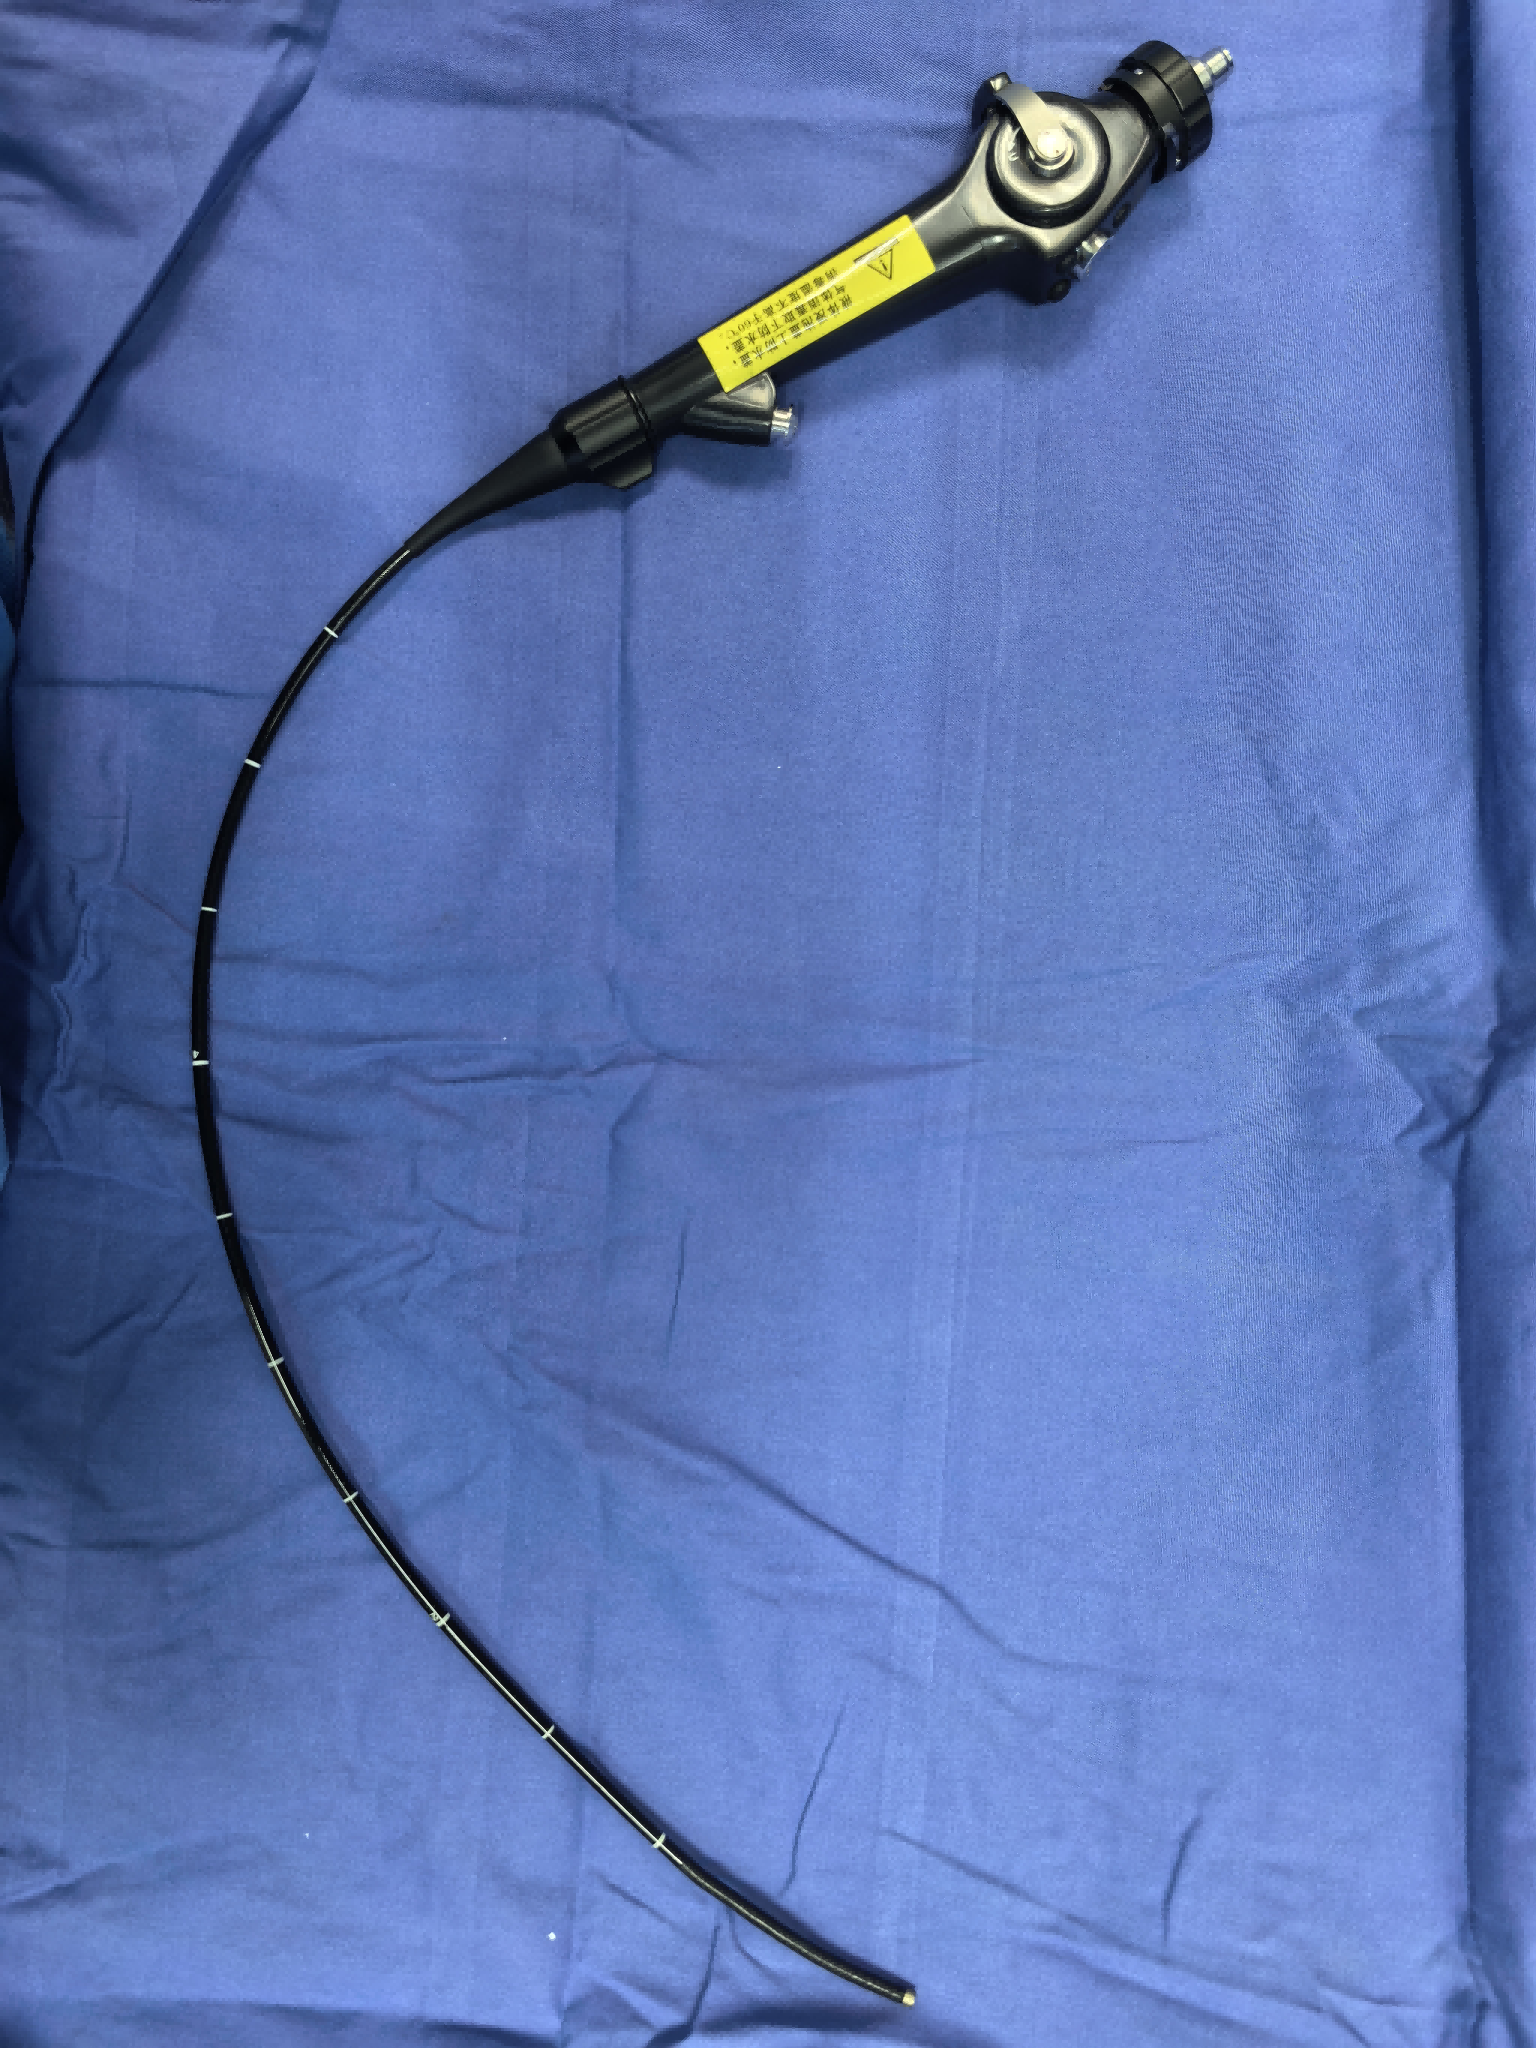

图2 床旁支气管镜

版权图片 不授权转载